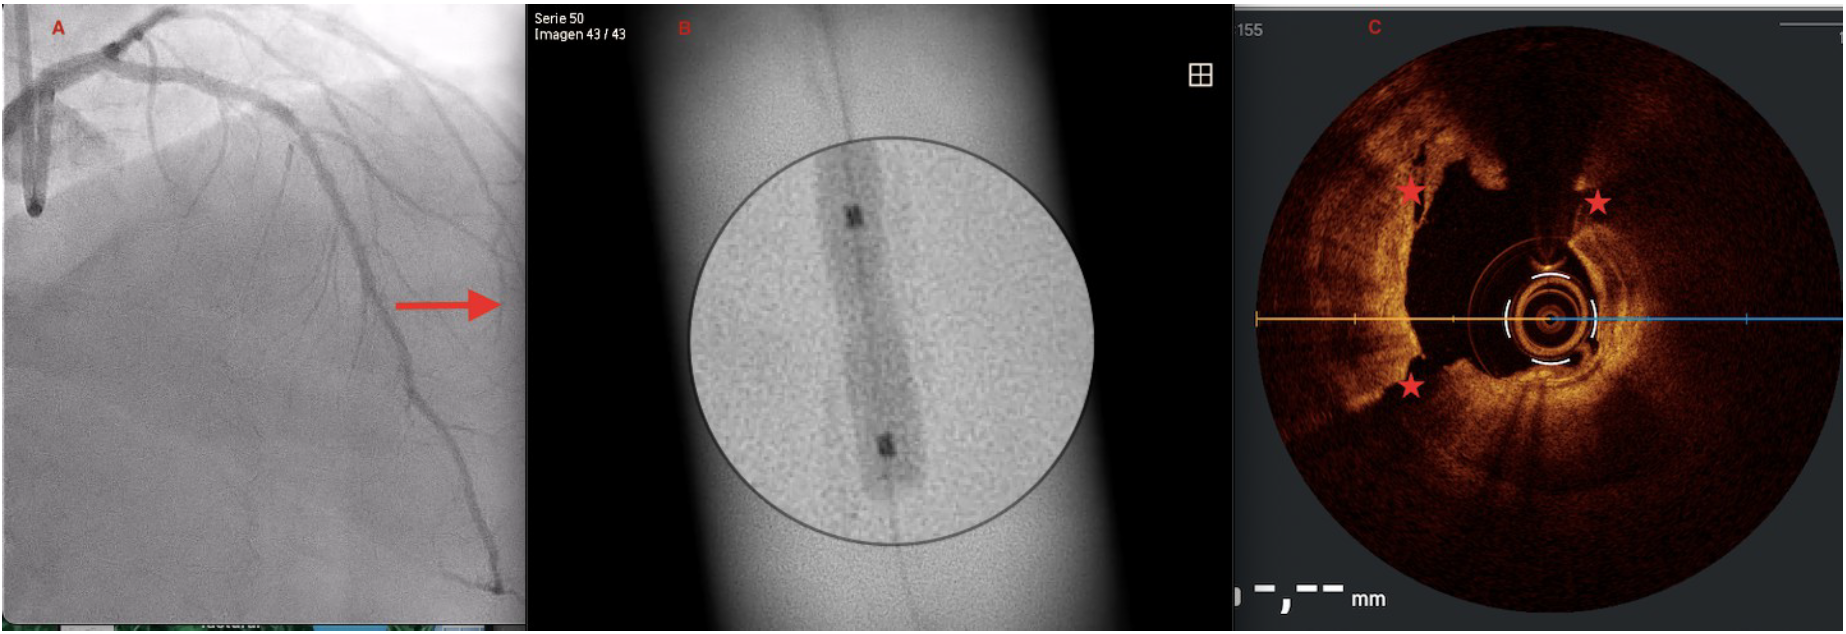

A 73-year-old man was hospitalized with acute coronary syndrome. Angiography showed severely calcified disease in the anterior descending artery and severe stenosis in the proximal, medial, and distal segments (Figure 1). Angioplasty was performed with an NC Trek Neo balloon (Abbott) with proper preparation of the plaque in the proximal and medial segments. Optical coherence tomography showed calcified plaque with a 360° ring and 1.2-mm thickness in the distal segment (Figure 2). Expansion attempts using a super high-pressure 2.5 x 10-mm OPN NC percutaneous transluminal coronary angioplasty (PTCA) balloon (SIS Medical) failed to fracture the calcification; rotational atherectomy with a Rotablator (Boston Scientific) was also unsuccessful. A 1.4-mm excimer laser coronary atherectomy catheter (Spectranetics) was also used (Figure 3) without fracturing the calcification, even after attempts with a super high-pressure balloon at 45 to 50 atm and being inflated for 40 to 60 seconds (Figure 4). Finally, a 3 x 28-mm Angiolite sirolimus-eluting stent (iVascular) was deployed in the proximal segments, followed by a 2.5 x 35-mm paclitaxel-eluting balloon (Medtronic) in the medial segment.